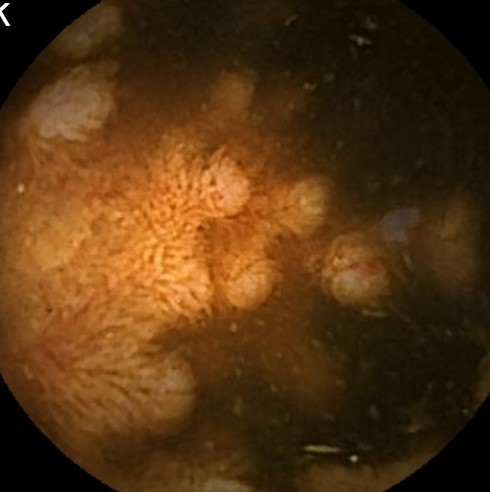

Capsule Endoscopy: Ileum Terminale, Lymphoid Hyperplasia

Capsule Endoscopy: Ileum Terminale, Lymphoid Hyperplasia. Just click on a picture!